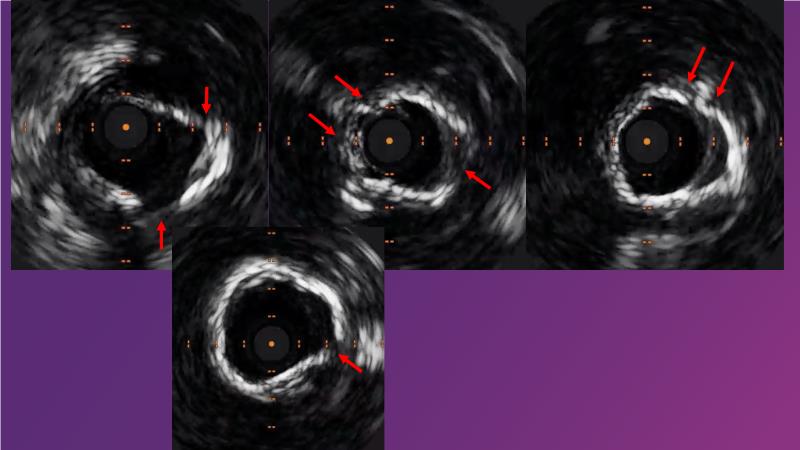

Watch this session to gain case-based insights on using DCBs in complex settings. Learn valuable tips and tricks for optimal DCB application, including the best timing and situations for their use. Discover how to effectively implement a hybrid strategy that combines DES and DCB when needed.

- To get a case based experience on how to use a DCB in complex settings

- To learn about tips and tricks on how and when to use a DCB: the ideal time and situation of DCB application in various complexities

- To utilise the hybrid strategy approach Combining DES and DCB when the situation demands